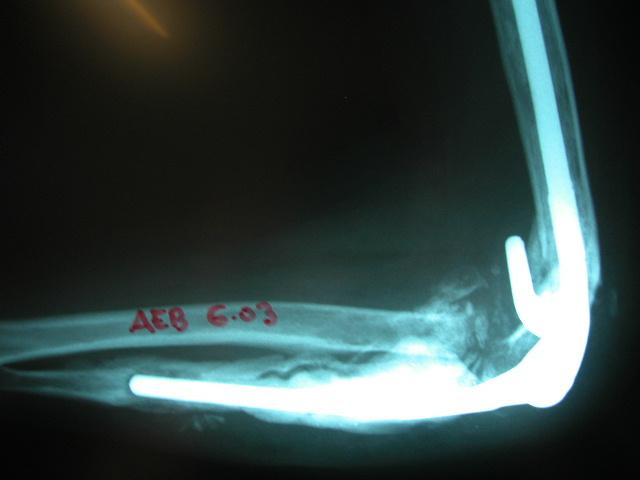

Fractura supracondílea de codo.

Fractura supracondílea de codo.Tras reducción y osteosíntesis.

Fractura supracondílea de codo. Tratamiento con agujas.